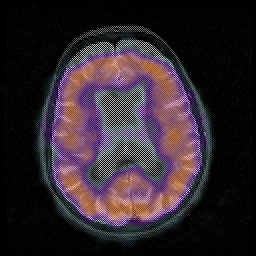

Huntington's Chorea, MR -- Slice #12

[Home][Help][Clinical] Slice 12